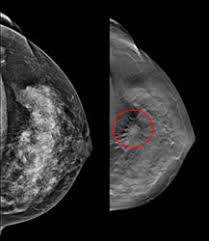

Benign, noncancerous masses can appear as a focal asymmetry. Breast cancer can present either as an area of focal asymmetry or when advanced can even present as a new asymmetry in breast size. Images are displayed as a series of thin slices that can. The outer edges of these cells look fuzzy or spiky (called spiculated). What does breast cancer look like on a mammogram? Diagnostic mammograms involve taking more views than screening mammograms. What does breast cancer look like on a mammogram? Not all women have calcifications in their breasts—but most do. This is why you should always talk to your doctor if you notice an unexplained change in the size of a breast. Ultimately, the news is good: Rather than an image that is formed from pictures taken from top to bottom and side to side like a. Even if you have a lump in only one breast, pictures will be taken of both breasts. They will look carefully at the mammogram to interpret the results.

Dense breast tissue appears solid. Essentially, mammograms turn a 3d object into a 2d object. Finding breast lumps and seeing change in the size and shape. Ultimately, the news is good: A number of studies have found that 3d mammograms find more cancers than traditional 2d mammograms and also reduce the number of false positives. A mammogram can show breast changes such as calcifications, masses, or other symptoms that might be cancer. Calcifications are calcium deposits within the breast tissue and they look like small white spots. Digital breast tomosynthesis (tomo), also known as 3d mammography, is a revolutionary new screening and diagnostic breast imaging tool to improve the early detection of breast cancer. American cancer society, 9 oct 2017. Ultrasound characterization of breast masses. indian journal of radiology and imaging. However, when the breast is compressed from top to bottom, the tissue in the upper breast can overlap tissue in the lower breast. Any area that does not look like normal tissue is a possible cause for concern. It appears to be developing in a concentric pattern.

That makes it easy to detect abnormalities, which generally show up as white. The look of breast cancer on a mammogram a tumor or lump will appear as a focused white area on the mammogram. Breast cancer can present either as an area of focal asymmetry or when advanced can even present as a new asymmetry in breast size. This is why you should always talk to your doctor if you notice an unexplained change in the size of a breast. However, in rare cases, breast cancer can be the cause of gynecomastia so, a full mammographic investigation is always necessary. Treatment typically involves some type of surgery and depends upon the staging of the. We'll show you breast cancer pictures to help you identify any physical traits of the condition. 3d mammography is capable of producing more detailed.

What does breast cancer look like on a mammogram? Screening mammograms have been used since the 1980s. On mammograms, dense breast tissue looks white. Bright spots on a mammogram that look like potential tumors could turn out to be overlapping tissues or a blood vessel folding over on itself, friedewald said. The outer edges of these cells look fuzzy or spiky (called spiculated). Moose & doc breast cancer, 21 may 2018. It is also an anatomic test, which means cancer is detected based on changes in how the breast anatomy looks. Food and drug administration in 2011. After a mammogram that didn't show anything, and a sonogram that found the lump, i was diagnosed with stage 2 breast cancer. Treatment typically involves some type of surgery and depends upon the staging of the. What does breast cancer look like on a mammogram? It appears to be developing in a concentric pattern. A mammogram can show breast changes such as calcifications, masses, or other symptoms that might be cancer.